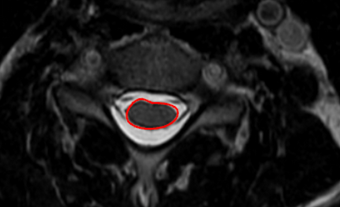

Image Type Cervical Spine X-Ray CT Scan MRI Scan Compression Ratio (AP diameter transverse diameter of cord) Cord Cross-Sectional Area (CSA) Cross-Sectional Canal Area Maximum Spinal Cord Compression Pavlov/Torg (Canal-Body Ratio) Sagittal Canal Diameter Spinal Cord Signal Change - T1 Hypointensity Spinal Cord Signal Change - T2 Hyperintensity (+ number of levels)